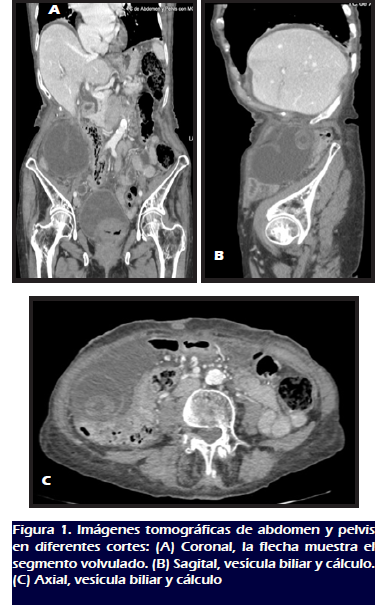

realizó una tomografía computarizada de abdomen y pelvis

con contraste endovenoso, la cual reveló una estructura

quística con un cálculo en su interior, además de

cambios inflamatorios significativos adyacentes, compatibles con

vólvulo vesicular. La vía biliar intra y

extrahepática se encontró de calibre normal sin factor

obstructivo. Se observó escasa ascitis y signos difusos de edema

mesentérico (Figura 1).

disponíamos de ecografía, el examen de elección en

nuestro caso fue la tomografía computarizada, que

evidenció el segmento volvulado de la vesícula biliar y

proporcionó apoyo diagnóstico prequirúrgico. Tras